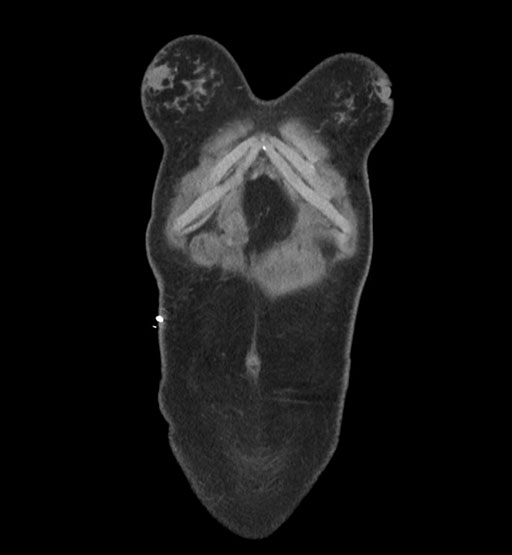

MRI T1

MRI T2